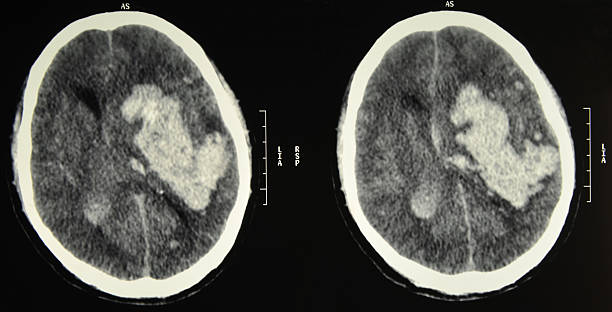

뇌출혈 전조증상 및 진단

뇌출혈이 발생하면 다양한 증상이 나타날 수 있습니다. 이러한 증상 중에서도 특히 편측 마비, 말 능력의 손실, 의식 변화 등이 나타날 경우 뇌출혈의 가능성을 고려해야 합니다. 이런 경우 즉시 의료기관을 찾아 진단 받아야 합니다.